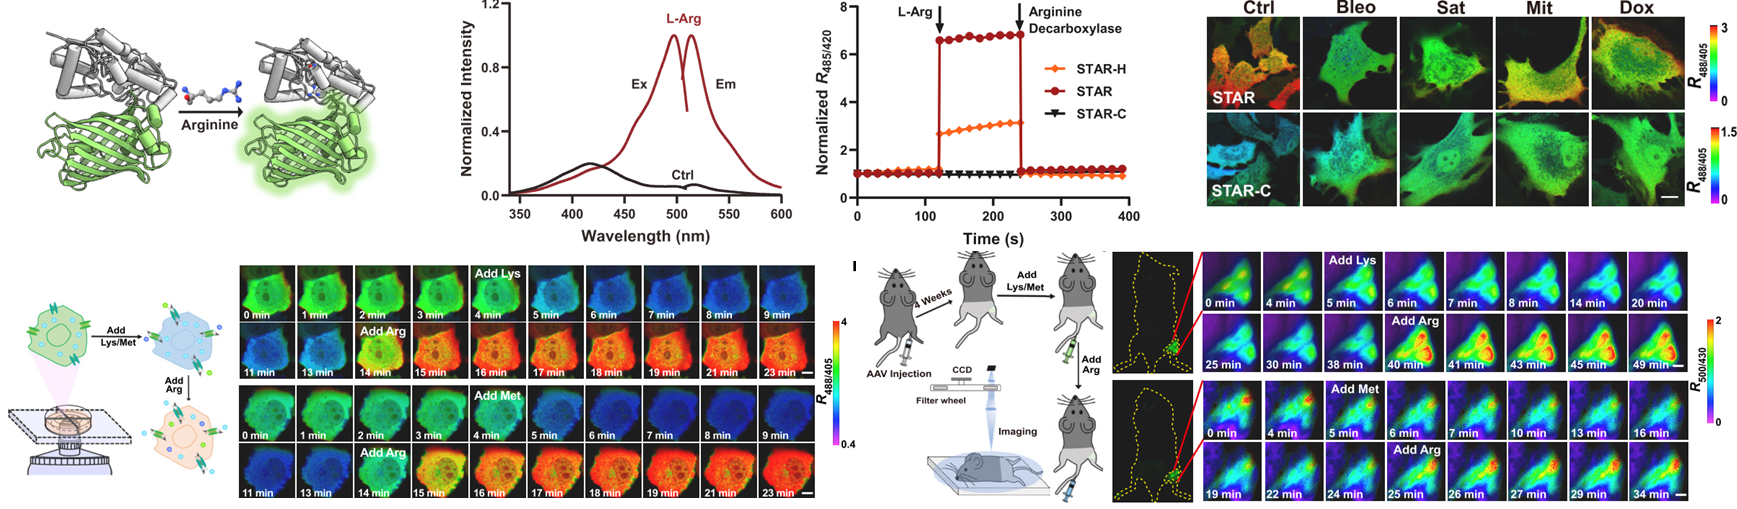

--------------------------------------------------------------------------------------------------------------------------------------------------- Lighting up arginine metabolism reveals its functional diversity in physiology and pathology 精氨酸是氨基酸中的“多面手”,不仅参与了蛋白质合成,也可分解产生一氧化氮、肌酸等一系列重要体内代谢物,还是氮平衡、尿素循环、血管舒张、免疫反应、肿瘤发生等多种生理病理过程的调节因子。然而,传统的生化方法难以进行原位、实时、动态、在体的分析。我们构建了一个高性能、遗传编码的精氨酸荧光探针“STAR”,成功实现了在单细胞及活体水平对精氨酸代谢的特异、灵敏地实时动态监测,并系统研究了精氨酸在氨基酸交换转运、巨噬细胞命运转变、基质细胞衰老调控及免疫疾病精准诊断中的重要作用(Cell Metabolism 2025, 37, 291).